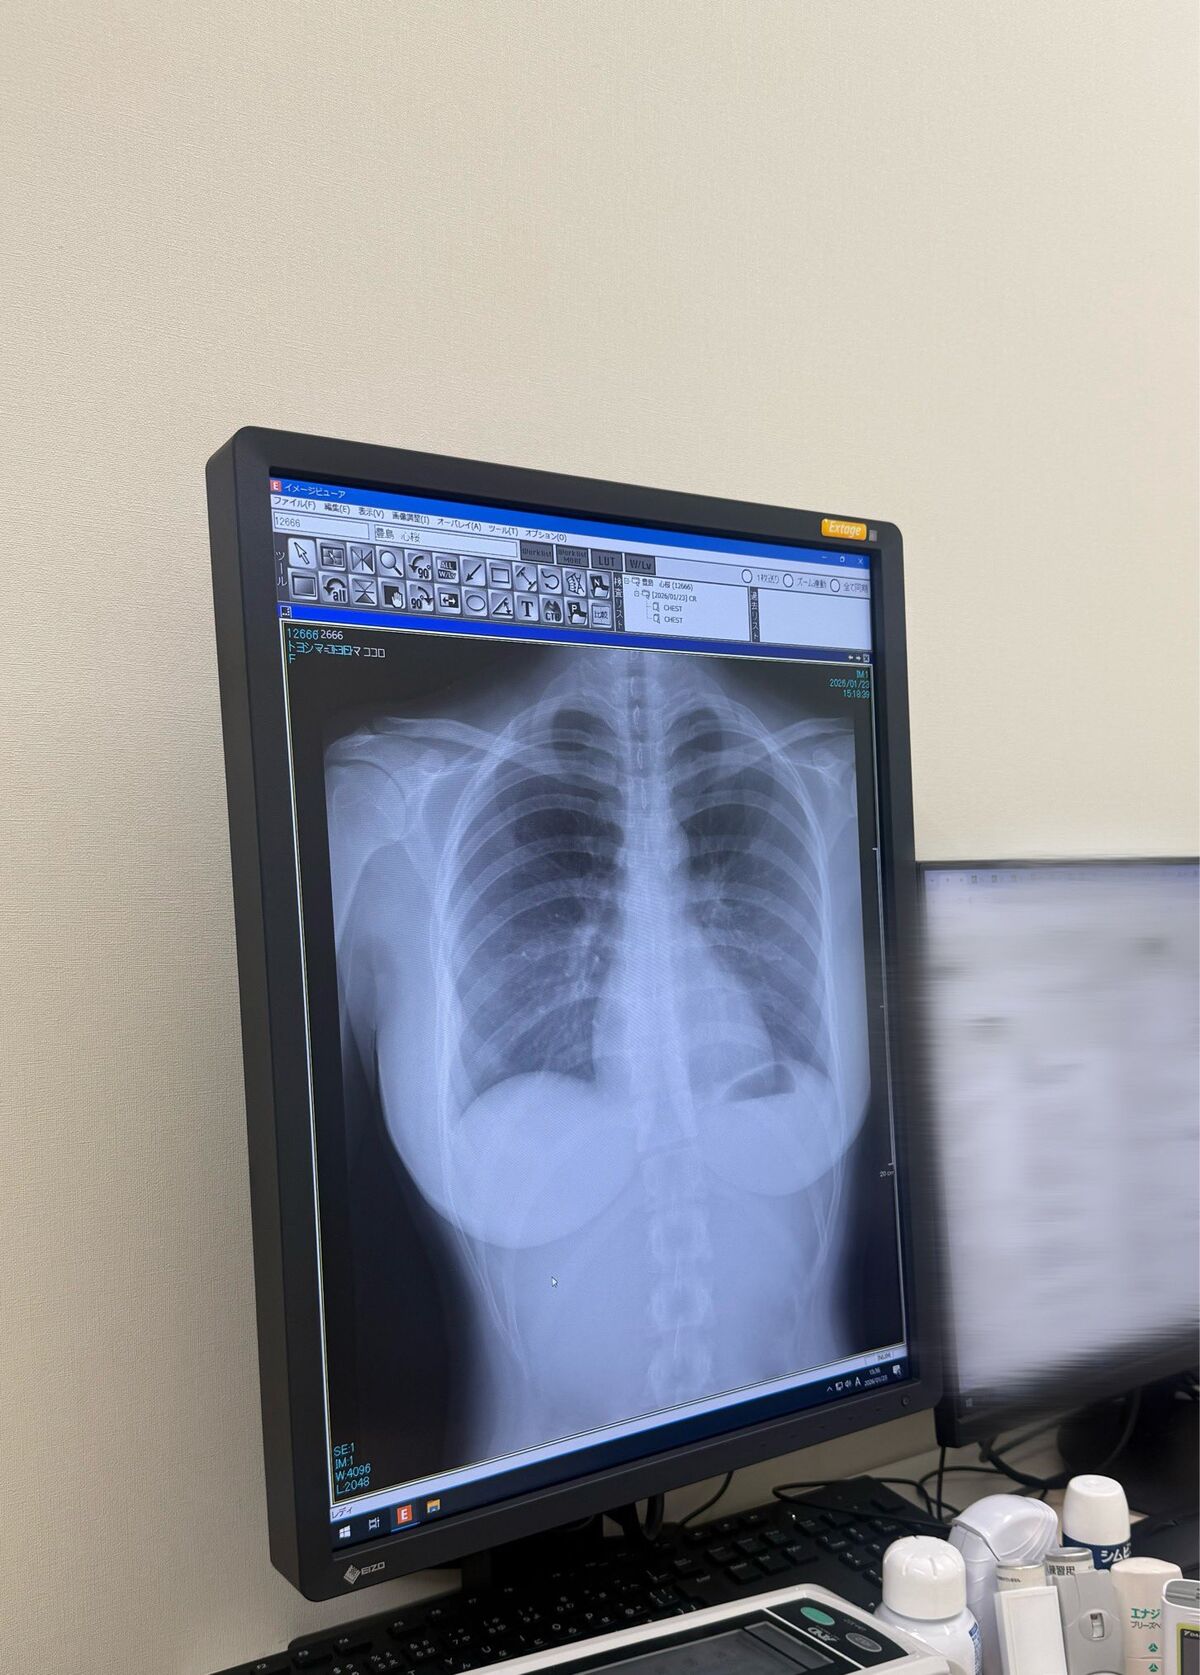

レントゲンがヤバいと話題に

肺綺麗でした pic.twitter.com/oprlolFN39

— 豊島 心桜 (@CocoroToyoshima) January 23, 2026

本当に綺麗な肺だ

推しのレントゲン公開

これ、自分のレントゲンと比べてマジで心臓とか肺が整ってて羨ましい

- 肺はきれいだけど、背骨曲がってんでねぇか

- 脊柱がやや湾曲してるっぽいけど、これくらいならあるあるかね